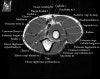

팔꿈치 관절의 MRI 단면 영상

- Sagittal section

1) Biceps Brachii tendon and Brachiallis muscles

2) Radial head for radiographically occult fractures

3) Distal Triceps tendon